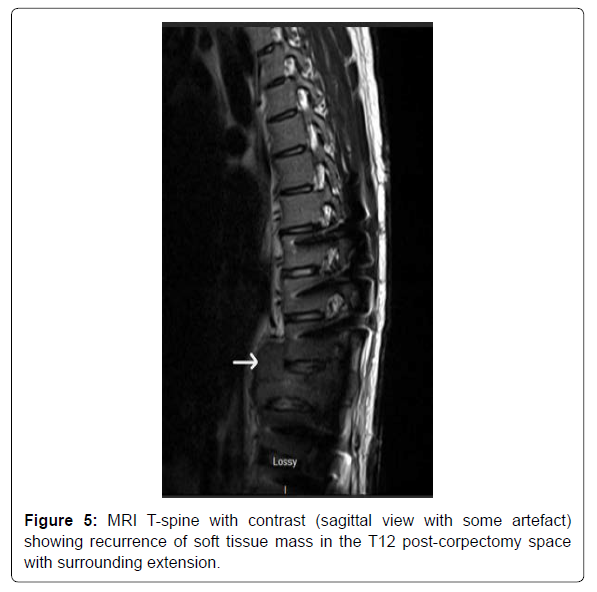

The patient did not follow up with any of the specialties after the discharge owing to poor socioeconomic support. He presented back to the hospital exactly three months after the discharge with symptoms of left and right-sided flank pain, worsening lower back pain, and fatigue. He was noted to have the dehiscence of the lower surgical incision site on examination. The patient was admitted for evaluation and management of a non-healing surgical wound. The patient was empirically started on IV ceftriaxone and Vancomycin for soft tissue infection. CT T and L-spine with contrast demonstrated recurrence of the soft tissue mass in the post-corpectomy space, extending into the central canal and measuring 8.3 x 6.5 cm, bilateral paraspinal fluid collections, and probable destructive lesions or bone erosions in the inferior endplate of T10-11 and the superior endplate of L1 (Figure 4). MRI T-spine with contrast had motion artifact related to cage graft, but within the limitations, showed similar findings of tumor recurrence (Figur 5). CT chest with contrast demonstrated extensive new soft tissue lung nodules, the largest nodule of 6mm, compared to CT from the previous admission, consistent with extensive lung metastases. The nodules were deemed too small for biopsy by the IR and the pulmonologist.

The neurosurgery team was consulted, and they took him for surgery on Day 5 of hospitalization. The operative findings were a massive recurrence of the tumor encircling the spinal cord and the expandable cage graft, and pseudoarthrosis of the graft. The patient underwent extensive surgical intervention involving washout and lavage of the infected thoracic wound, extensive re-resection of the tumor to decompress the neural elements, removal of the graft and replacement with a larger Ulrich cage graft, placement of crosslink at the laminectomy site, and reclosure of the wound. The biopsy returned positive for the giant cell tumor without evidence of malignant transformation (Figure 6). Wound cultures only grew Staphylococcus epidermidis, and antibiotics were narrowed down to ceftriaxone in the context of a negative nasal MRSA screen and eventually stopped after 8 days.